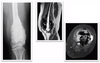

# Princípios básicos de tumores ósseos - Com base na imagem, classifique de acordo com Enneking:

- **B1 → latente** (*presença de esclerose*)

33

- **B2 → ativo** (*afila a cortical*)

34

- **B3 → agressivo** (*rompe a cortical*)

35

# Princípios básicos de tumores ósseos - De acordo com a imagens e as características listadas abaixo, classifique de acordo com Enneking: - Tumor maligno - Baixo grau - Sem metástase

- Baixo grau → **I** - Extracompartimental (extensão para partes moles visto na radiografia) → **B** - Classificação de Enneking → **I B**

36

# Princípios básicos de tumores ósseos - De acordo com a imagens e as características listadas abaixo, classifique de acordo com Enneking: - Tumor maligno - Osteossarcoma clássico de alto grau na biópsia - Sem metástase

- Alto grau → **II** - Extracompartimental (extensão para partes moles visto na radiografia) → **B** - Classificação de Enneking → **II B**